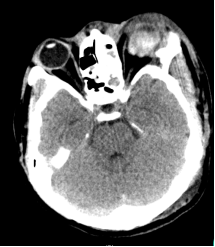

左眼眼球损伤,玻璃体积血,眼内结构混乱